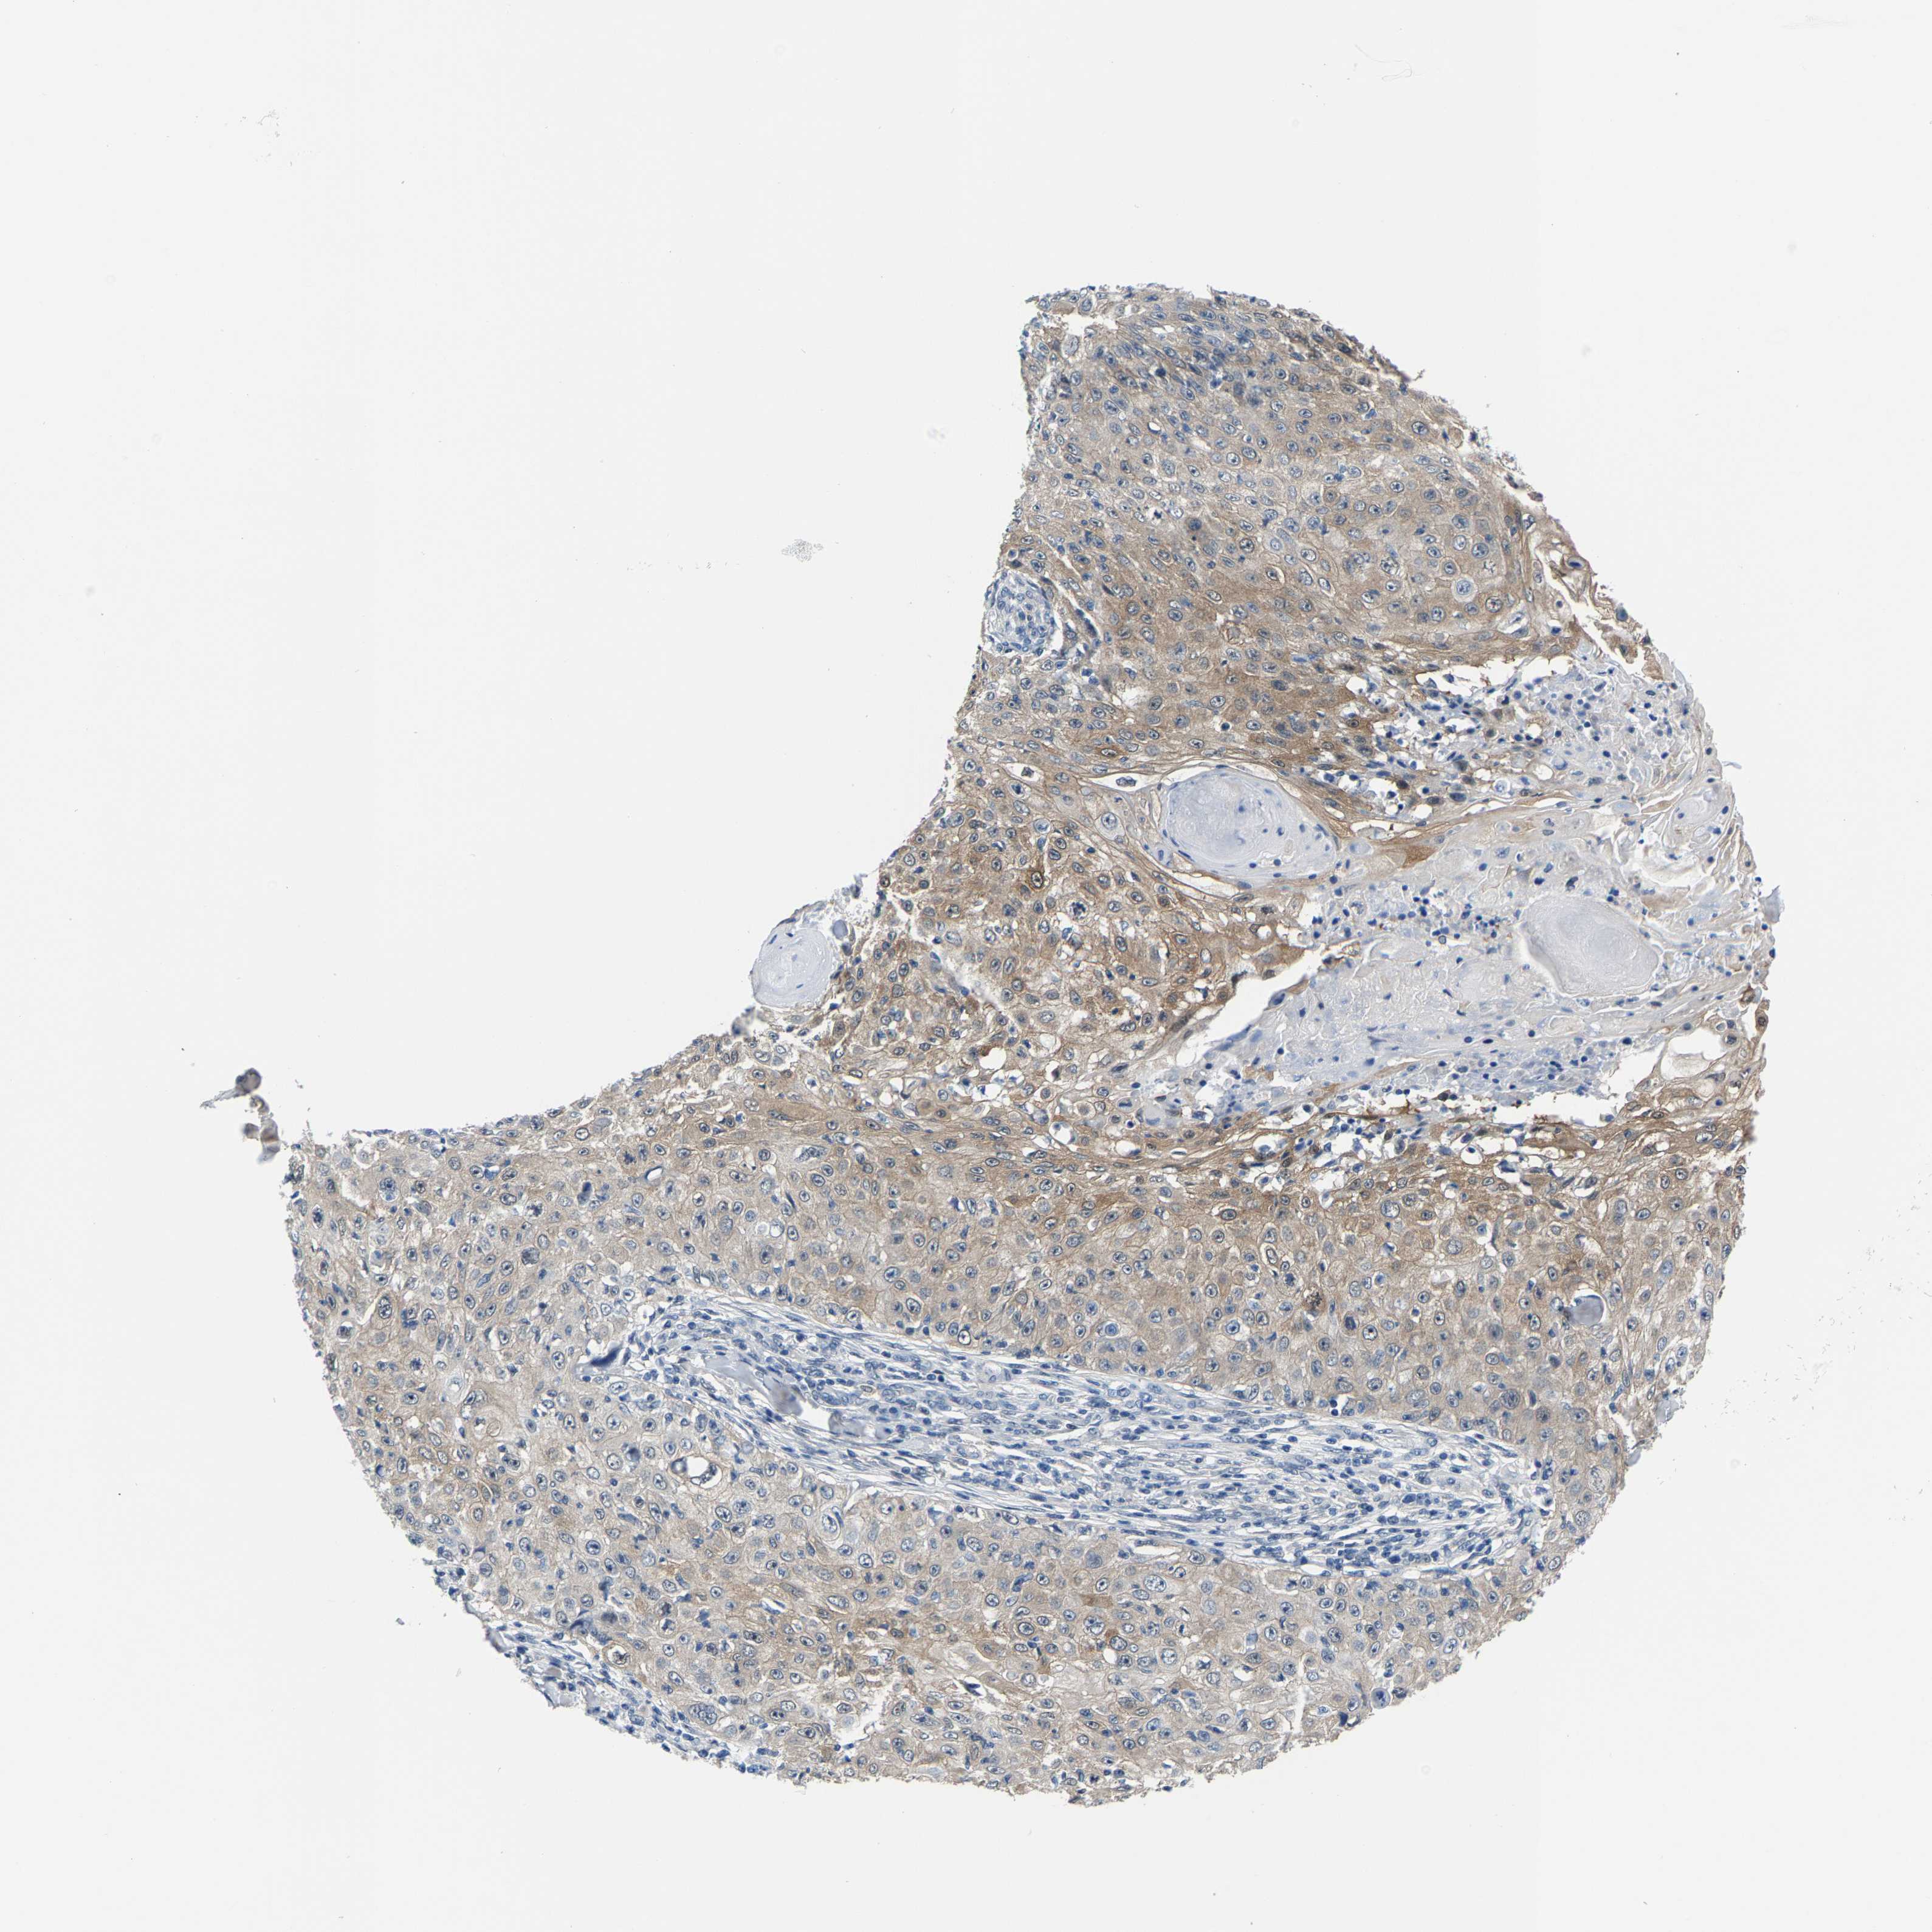

SKIN CANCER - Protein expressioni

A mouse-over function shows sample information and annotation data. Click on an image to view it in a full screen mode. Samples can be filtered based on level of antibody staining by selecting one or several of the following categories: high, medium, low and not detected. The assay and annotation is described here.

Each image is clickable and will lead to virtual microscopy that enables deeper exploration of all samples and also displays staining intensity scores, fraction scores and subcellular localization as well as patient and tissue information for each sample.

Antibody HPA019949

Staining

High

Medium

Low

Not detected

Intensity

Strong

Moderate

Weak

Negative

Quantity

>75%

75%-25%

<25%

None

Location

Nuclear

Cytoplasmic/membranous

Cytoplasmic/membranous,nuclear

Squamous cell carcinoma in situ, NOS

Squamous cell carcinoma, NOS

Squamous cell carcinoma, metastatic, NOS

Basal cell carcinoma